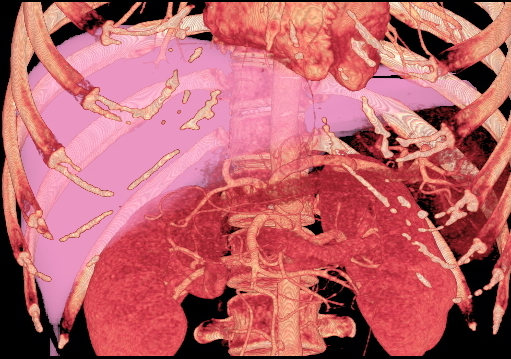

잠재적 기증자 평가를 위해 수행된 CT 스캔. 이 이미지는 특이한 간 동맥 변이를 보여준다.

전산 단층 촬영술(computed tomography)로 생성된 부피 렌더링 이미지로, 잠재적 기증자의 간 부피를 평가하는 데 사용할 수 있음